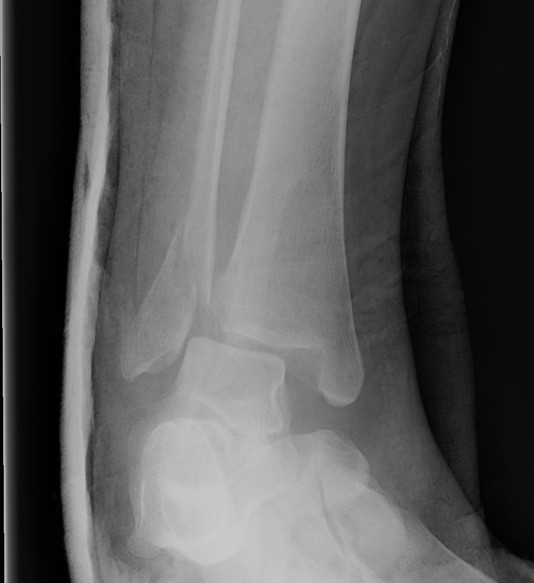

X-ray assessment

3 standard views

AP / Lateral / Mortise

Mortise

- AP with foot internally rotated

- should be symmetrical space around talus

Ankle Mortise ViewMortise